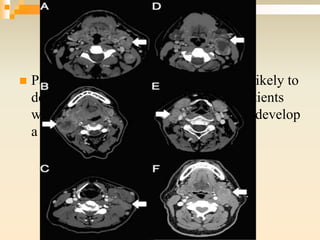

 Patients with matted nodes were more likely to

develop distant metastases, whereas patients

with normal nodes were more likely to develop

a local recurrence